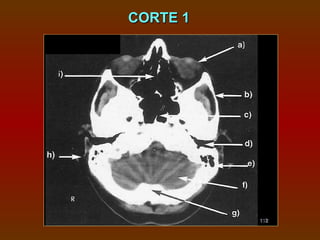

CORTE 1

a) Órbita (observe a elevada densidade do cristalino

na margem anterior do globo ocular)

b) Arco zigomático

c) Seio esfenoidal

d) Canal acústico externo

e) Processo mastóideo

f) Cerebelo

g) Protuberância occipital interna

h) Seios etmoidais